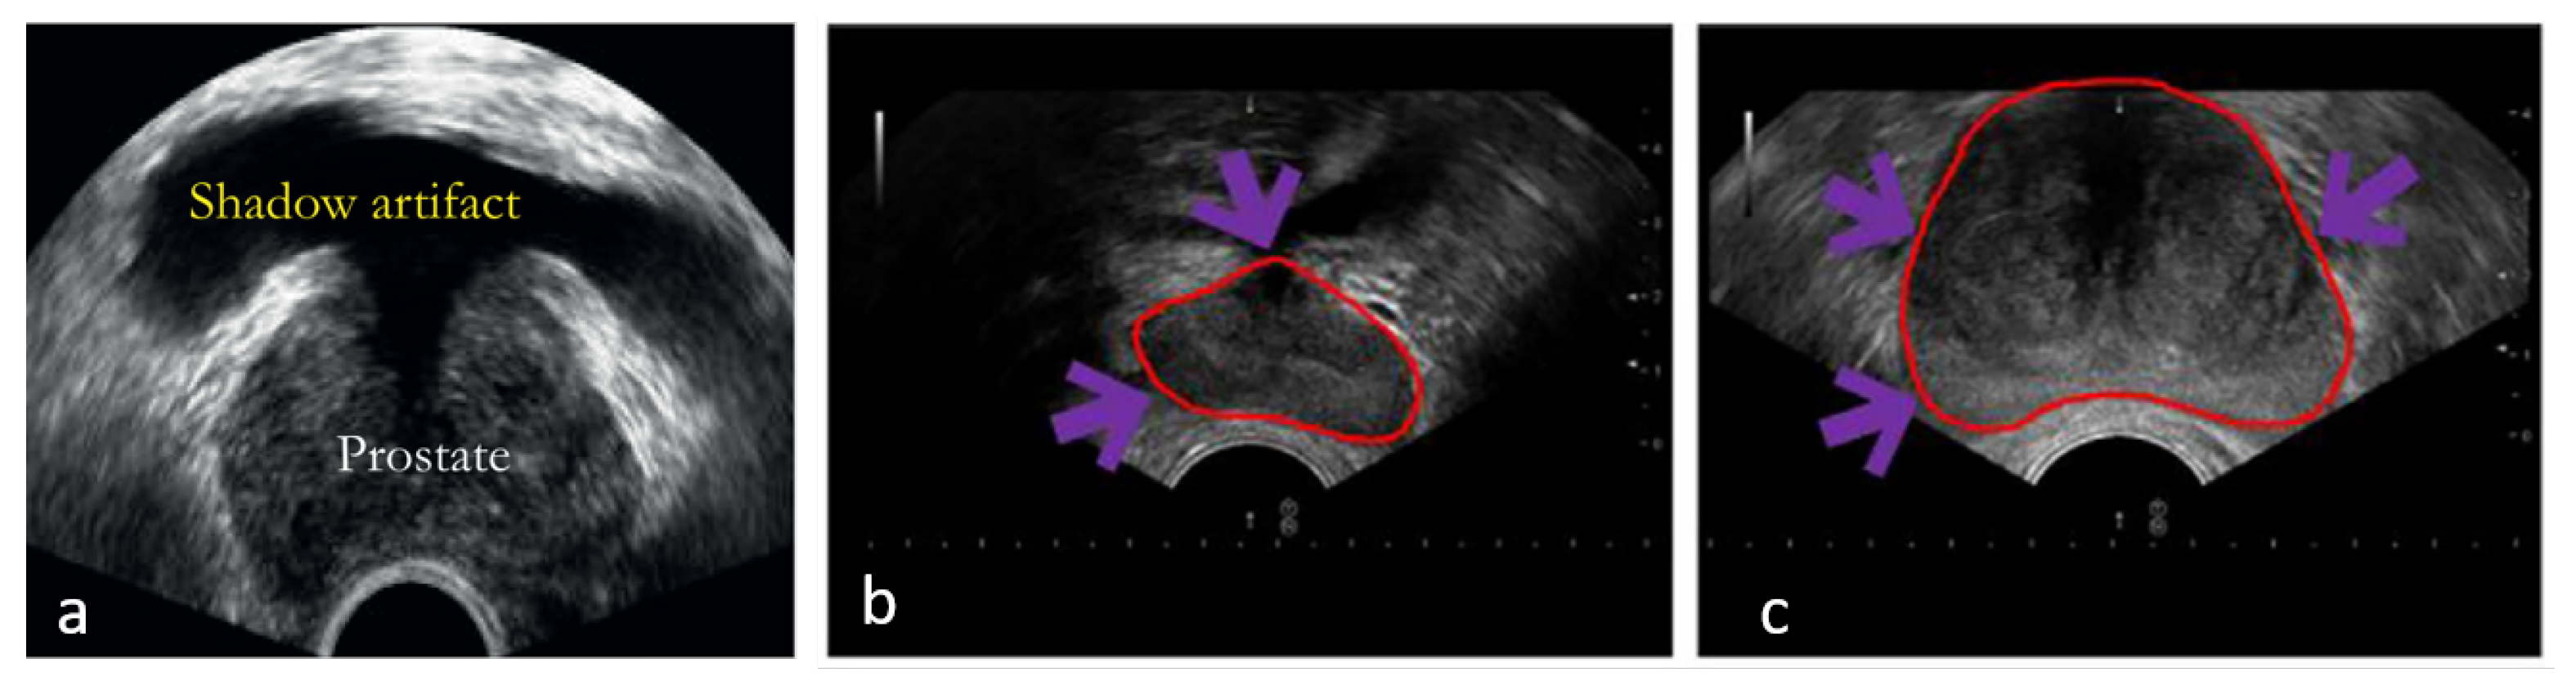

- Xu, X.; Sanford, T.; Turkbey, B.; Xu, S.; Wood, B.J.; Yan, P. Shadow-Consistent Semi-Supervised Learning for Prostate Ultrasound Segmentation. IEEE Trans. Med. Imaging 2022, 41, 1331–1345. [Google Scholar] [CrossRef] [PubMed]

| Xu et al. (2022) [39] | Modified U-Net that is trained by shadow-enhanced images and a modified feature space. |